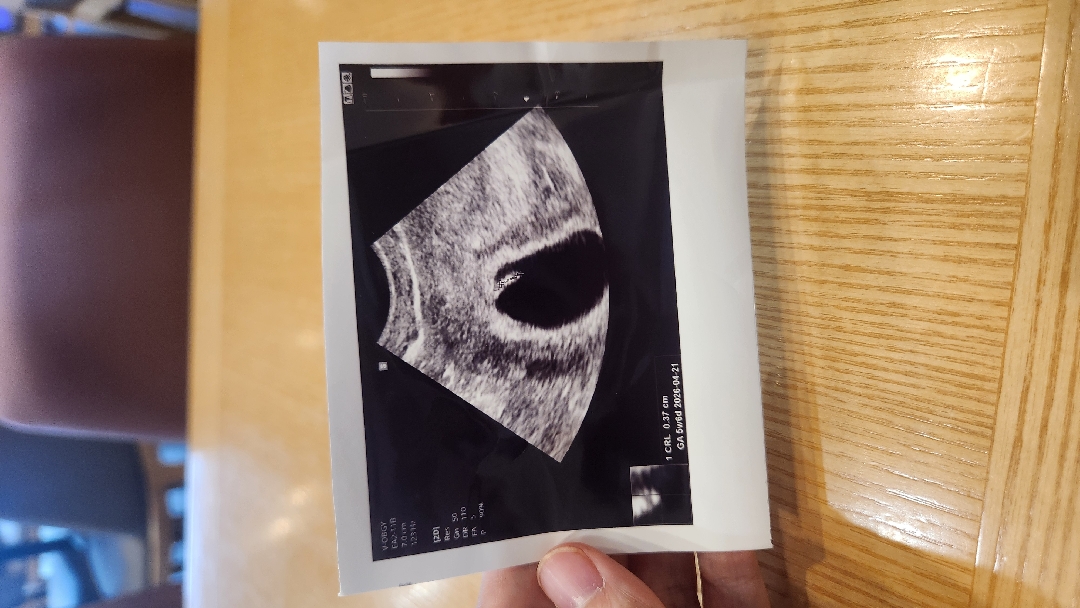

6주차 초음파 보고 왔어요!

6주 4일차인데 이 쪼꼬미가 아기래요.., 나름 심소도 우렁차고(?)너무 웃기고 귀엽네요..!둘찌인데 이런 모양은 첨봐여..다들 동그랗던데;;